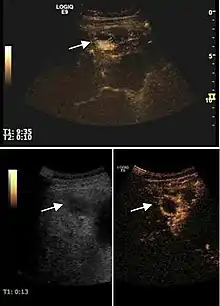

However, it is able to detect the appearance of new lesions and to assess the occurrence of any complications of disease progression (ascites or portal vein thrombosis). Color Doppler ultrasound can be useful sometimes being able to show the presence of intratumoral vasculature as a sign of incomplete therapy or intratumoral recurrence. The absence of Doppler signal does not exclude the presence of viable tumor tissue. CEUS exploration, by its ability to enhance intra-lesion microcirculation, has proved its utility in monitoring therapeutic efficacy. Its indications are defined for HCC ablative treatments (pre, intra and post-therapy), while monitoring of systemic therapies of HCC and metastases are not validated indications at this time, but with proved efficacy in extensive clinical trials (Claudon et al., 2008). CEUS examination cannot completely replace the other imaging diagnostic methods currently in use because of the known limitations of the ultrasound method (operator/ equipment dependent, ultrasound examination limitations). In addition to bloating, in cancer patients post-therapy steatosis occurs, which prevent deep visibility. Spiral CT scan remains the method of choice in monitoring cancer therapies because it provides an overview of tumor extension and it is not limited by bloating or steatosis.

2D ultrasound, Doppler ultrasound and especially CEUS can play an important role in pretherapeutic staging, particularly when sectional imaging investigations (CT, MRI) provide uncertain results or are contraindicated. During the interventional procedure, ultrasound allows guidance of the needle into the tumor. CEUS allows guidance in areas of viable tissue and avoids intratumoral necrotic areas. CEUS also allows assessment of therapeutic effect immediately post-procedure (with the possibility of reintervention in case of partial response) . To accurately assess the effectiveness of treatment it is mandatory to compare the tumor diameter before therapy with the ablation area. The volume of damaged tissue must be higher than the initial tumor volume. CEUS appearance is that of central nonenhanced area showing a peripheral homogeneous hyperenhanced rim due to post-procedure inflammation. 24 hours after the procedure the inflammatory peripheral rim is thinning and the necrotic area appears larger than at the previous examination. Thus, a possible residual tumor may appear more evident. Residual tumor has poorly defined edges, irregular shape, and the tumor diameter is unchanged. Residual tumor tissue is evidenced at the periphery of the tumor as an eccentric area behaving as the original tumor at CEUS examination, with arterial hyperenhancement and portal and late wash-out. Ultrasound examination 24 hours after the procedure, including CEUS, can show apart from the character of the lesion any potential post-intervention complications (e.g. active bleeding).

In the first days after RFA both CEUS and spiral CT have low sensitivity in assessing therapeutic efficacy. CT sensitivity 24 hours post-therapy is reported to be even lower than CEUS. Difficulties in CEUS examination result from post-lesion hyperemia, presence of intratumoral air, ultrasound limitations (too deep lesion or the presence of fatty liver) or lack of patient's cooperation (immediately after therapy). For this reasons contrast imaging (CT or CEUS) control should be performed one month after ablation to confirm the result of the therapy.

Local recurrence is defined as recurrence of a hyperenhanced area at tumor periphery in the arterial phase, with portal and late wash-out. Sometimes, especially for HCC treated by alcoholization (PEI) hyperenhanced septa or vessels can be shown inside the lesion.